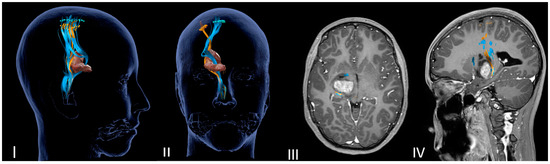

Figure 1.

(I–IV) Neuronavigated transcranial magnetic stimulation pre-op study. (I,II) A 3D reconstruction of the nTMS data that shows cortical maps of the right spinal tract (CST) for the hand (green) and foot (yellow) and its relationship with the thalamopeduncular tumor of Case B. (III,IV): The brain MRI merged with the nTMS data shows that the cortical spinal tract (CST) runs antero-laterally with respect to a right thalamopeduncular tumor.